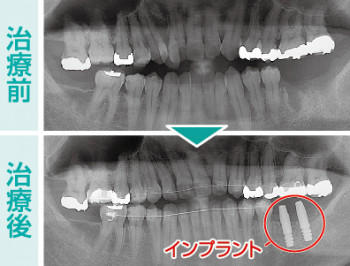

約2年間でしっかり咀嚼できる機能的な歯並びになったところで、左側臼歯部に2本のインプラントを埋入しました。右側臼歯部も1本欠損していますが、ここにはインプラントを埋入せず現状維持でいくこととしました。

天然歯における不正な歯並びには歯列矯正を行い、歯を失った箇所にはインプラント治療を行うことで、機能性に優れた咬合状態へと回復させてあげられます。

- 全顎矯正治療及びインプラント治療